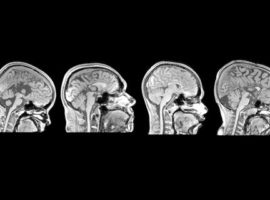

Outra linha de pesquisa importante desenvolvida pelo IDOR na área neurociência é a de neuroimagem, em particular aplicada ao estudo da plasticidade cerebral, isto é, da capacidade que o cérebro humano tem de se adaptar a situações adversas. A integração entre os resultados de exames de imagens e dados clínicos, genéticos e laboratoriais permite estudar as doenças do sistema nervoso central de forma aprofundada, em três vertentes principais: doenças do neurodesenvolvimento, reabilitação e plasticidade no envelhecimento.

Com uso de exames de ressonância magnética funcional, os pesquisadores conseguem identificar as rotas de conexão entre as diferentes partes do cérebro saudável e em situações patológicas. Entre as condições estudadas estão a disgenesia do corpo caloso, os acidentes vasculares cerebrais e a síndrome do membro fantasma, que pode surgir após uma amputação.